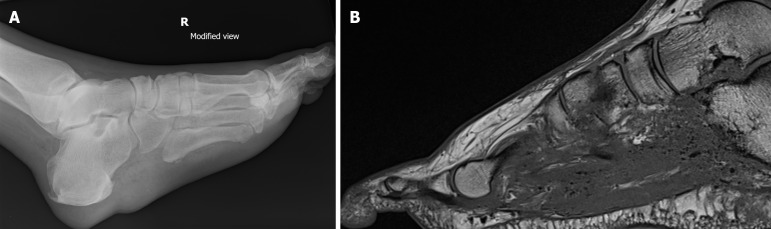

Abstract Image